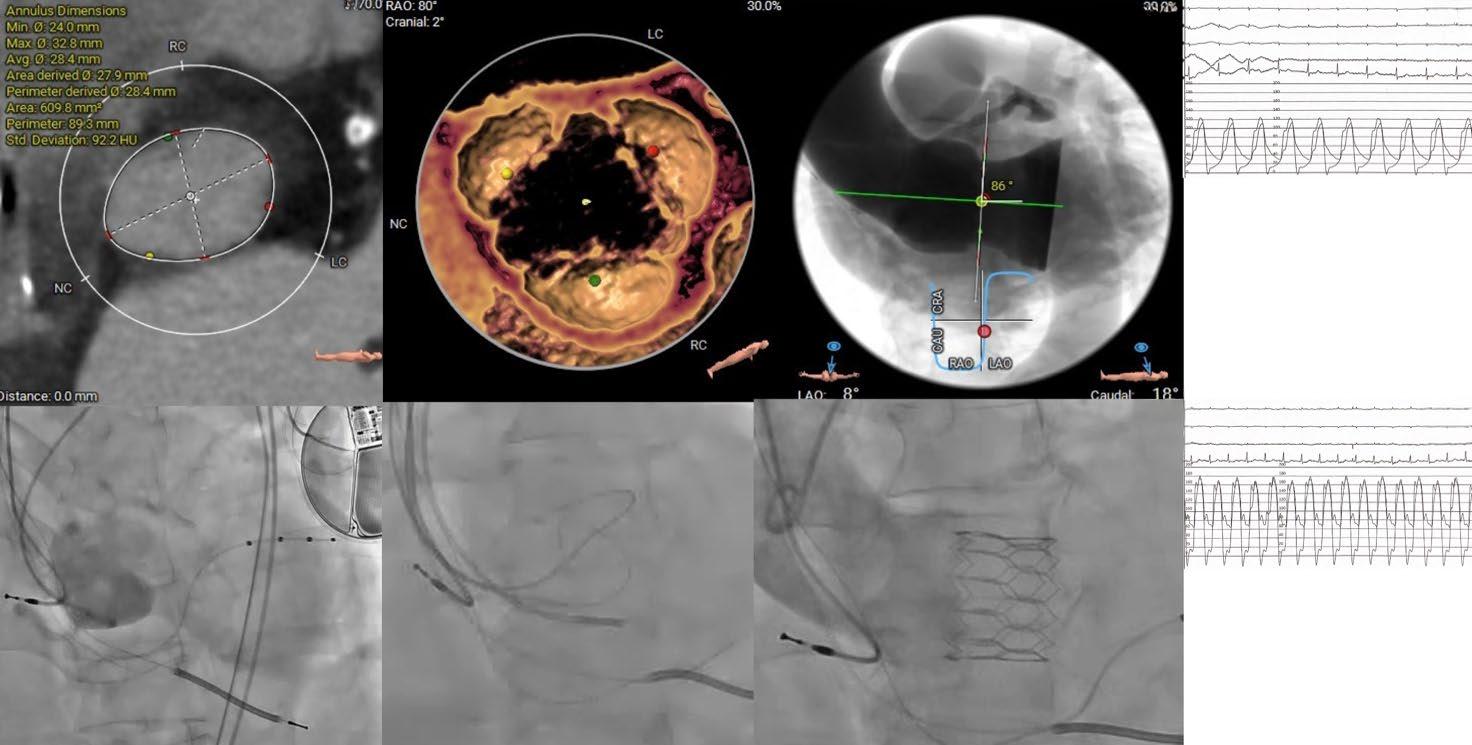

All peer review is double blind.

74 Editor's Pick: Transcatheter Aortic Valve Implantation and Pure Non-Calcified Aortic Regurgitation

Marrone and Ielasi 86 Drug-Coated Balloons in Percutaneous Coronary Interventions